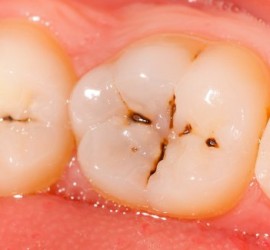

Ретроградный кариес. Кариозный процесс разрушает дентин со стороны пульпы. Наблюдается при наличии интактной, кариозной и пломбированной коронки, а также в случае гангрены пульпы кариозного и травматического происхождения. Со стороны полости пульпы идет процесс распада дентина за счет функции микроорганизмов и протеолитических ферментов. Ретроградный кариес может иметь место при хроническом пролиферативном […]